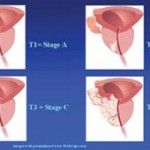

Τα στάδια του αδενοκαρκινώματος του προστάτη

Κατηγορίες επικινδυνότητας

Ο συνδυασμός των τριών παραμέτρων (PSA – Gleason score – TNMStage) κατατάσσει τους ασθενείς σε τρεις κατηγορίες, τους χαμηλής, μέσης και υψηλής επικινδυνότητας.

Ο συνδυασμός των τριών παραμέτρων (PSA – Gleason score – TNMStage) κατατάσσει τους ασθενείς σε τρεις κατηγορίες, τους χαμηλής, μέσης και υψηλής επικινδυνότητας.

Σε κάθε κατηγορία συνιστώνται ή αντενδείκνυνται κάποιες μέθοδοι αντιμετωπίσεως – θεραπείας.

- Χαμηλής επικινδυνότητας (Low Risk): Ασθενείς με PSA λιγότερο από 10 ng/ml (PSA<10), έχουν Gleason Score μικρότερο ή ίσο του 6 (Gleason <= 6) και είναι σταδίου T1 ή Τ2a.

Οι ασθενείς χαμηλής επικινδυνότητας, λόγω του ότι βρίσκονται σε πρώιμο στάδιο, μπορούν να εφαρμόσουν οποιαδήποτε χειρουργική ή ακτινοθεραπευτική μέθοδο – τεχνική σαν μονοθεραπεία (ριζική και αποκλειστική θεραπευτική αντιμετώπιση), αποδεχόμενοι βέβαια τις παρενέργειες και επιπλοκές της κάθε μιας, τις οποίες θα τους εξηγήσει ο ουρολόγος τους.

Η θεραπεία περιορίζεται ΜΟΝΟ στον προστάτη αδένα, γιατί οι πιθανότητες εξωπροστατικής διασποράς είναι ελάχιστες έως μηδενικές.

- Μέσης επικινδυνότητας (Medium Risk): Ασθενείς με PSA από 10 – 20 ng/ml (PSA 10 – 20), έχουνGleason Score ίσο με 7 (Gleason = 7) και είναι σταδίου Τ2b.

Οι ασθενείς μέσης επικινδυνότητας, επειδή βρίσκονται σε μέτριας βαρύτητας στάδιο, μπορούν να εφαρμόσουν συνδυασμό τουλάχιστον δύο μεθόδων από τις τρεις ακόλουθες: τη χειρουργική, την ακτινοθεραπεία και την ορμονοθεραπεία (με σχεδόν όλες τις υποκατηγορίες τους). Φυσικά θα ενημερωθούν από τον ουρολόγο τους για τις παρενέργειες και επιπλοκές κάθε συνδυασμού. Η θεραπεία περιλαμβάνει κυρίως τον προστάτη αδένα, αλλά προστατευτικά καλύπτει και τους περιβάλλοντες ιστούς μαζί με τους ανάλογους λεμφαδένες επειδή υπάρχει αυξημένη πιθανότητα διηθήσεως της κάψας του αδένος, των σπερματοδόχων κύστεων και ίσως ύπαρξη μικρομεταστάσεων στους επιχώριους λεμφαδένες.

Υψηλής επικινδυνότητας (High Risk): Ασθενείς με PSA μεγαλύτερο των 20 ng/ml (PSA > 20), έχουνGleason Score ίσο ή μεγαλύτερο του 8 (Gleason >= 8) και είναι σταδίου T2c, Τ3 ή Τ4.

Οι ασθενείς υψηλής επικινδυνότητας, επειδή βρίσκονται σε σχετικά προχωρημένο στάδιο, πρέπει να εφαρμόσουν συνδυασμό ορμονοθεραπείας και εξωτερικής ακτινοθεραπείας και ίσως επικουρικά κάποια χειρουργική μέθοδο. Σε αυτούς, υπάρχει ανάγκη γενικότερης θεραπείας του οργανισμού και όχι μόνο τοπικής στον προστάτη αδένα, γιατί οι πιθανότητες υπάρξεως εξωπροστατικής διασποράς του αδενοκαρκινώματος είναι πολύ μεγάλες (σχεδόν βέβαιες).